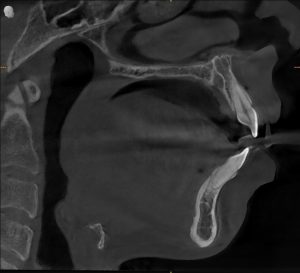

A detailed clinical and radiographic evaluation revealed the silent contributors behind his sleep struggles:

- Retrognathic mandible (recessed lower jaw) — restricting airway space

- Large, low-lying tongue — collapsing backward during sleep

- Airway analysis: Moderate to severe constriction

- Facial profile: Skeletal imbalance linked to airway narrowing

The diagnosis was clear:

His airway wasn’t just closing during sleep — it was structurally compromised.